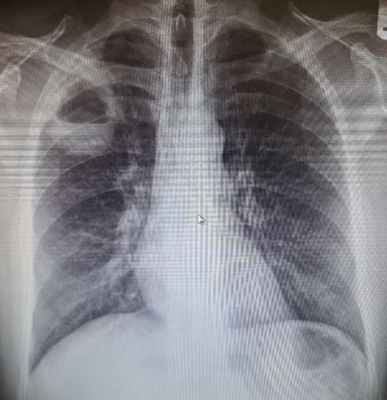

По направлению от врача-терапевта, пациентке была выполнена рентгенография органов грудной клетки, в 2-х проекциях.

Протокол исследования:

При анализе полученных снимков была выявлена толстостенная полость с наличием горизонтального уровня жидкости.

Заключение: Рентгенологическая картина абсцесса правого лёгкого, с наличием уровня жидкости.